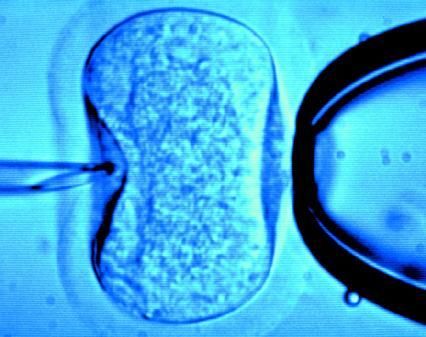

據(jù)英國《每日郵報(bào)》1月18日?qǐng)?bào)道,英國一位60歲老婦將成為英國接受試管受精最年長(zhǎng)者。這位老婦名叫蘇珊·托勒夫森,是一位退休教師,到今年10月她就滿60歲了。2008年,蘇珊曾去俄羅斯接受試管受精,在英國生下了她的第一個(gè)孩子。

倫敦哈利街的私人診所是英國試管嬰兒手術(shù)成功率較高的醫(yī)院之一,醫(yī)生們?cè)谏现芤煌鈳椭K珊·托勒夫森進(jìn)行第二次人工受孕。通常情況下,私人診所只在特殊情況下給50歲以上的婦女進(jìn)行試管受精,例如,患者仍然有月經(jīng)周期。這件事引起了絕經(jīng)后婦女是否有生育權(quán)利的倫理大討論,現(xiàn)在要求提高生育治療年齡上限的呼聲越來越高。

現(xiàn)在,蘇珊·托勒夫森一家人很幸福,丈夫尼克·邁耶是一位公司經(jīng)理,比她小11歲,他們的女兒今年2歲。專家表示,蘇珊很健康,她的女兒如果能有一個(gè)兄弟姐妹會(huì)更好,于是蘇珊想再次接受試管受精!缎瞧谌锗]報(bào)》獲悉,倫敦哈利街私人婦女診所的高級(jí)工作人員已經(jīng)同意為蘇珊做試管受精,還決定幫助另一位57歲的老婦受孕。(海瀾)